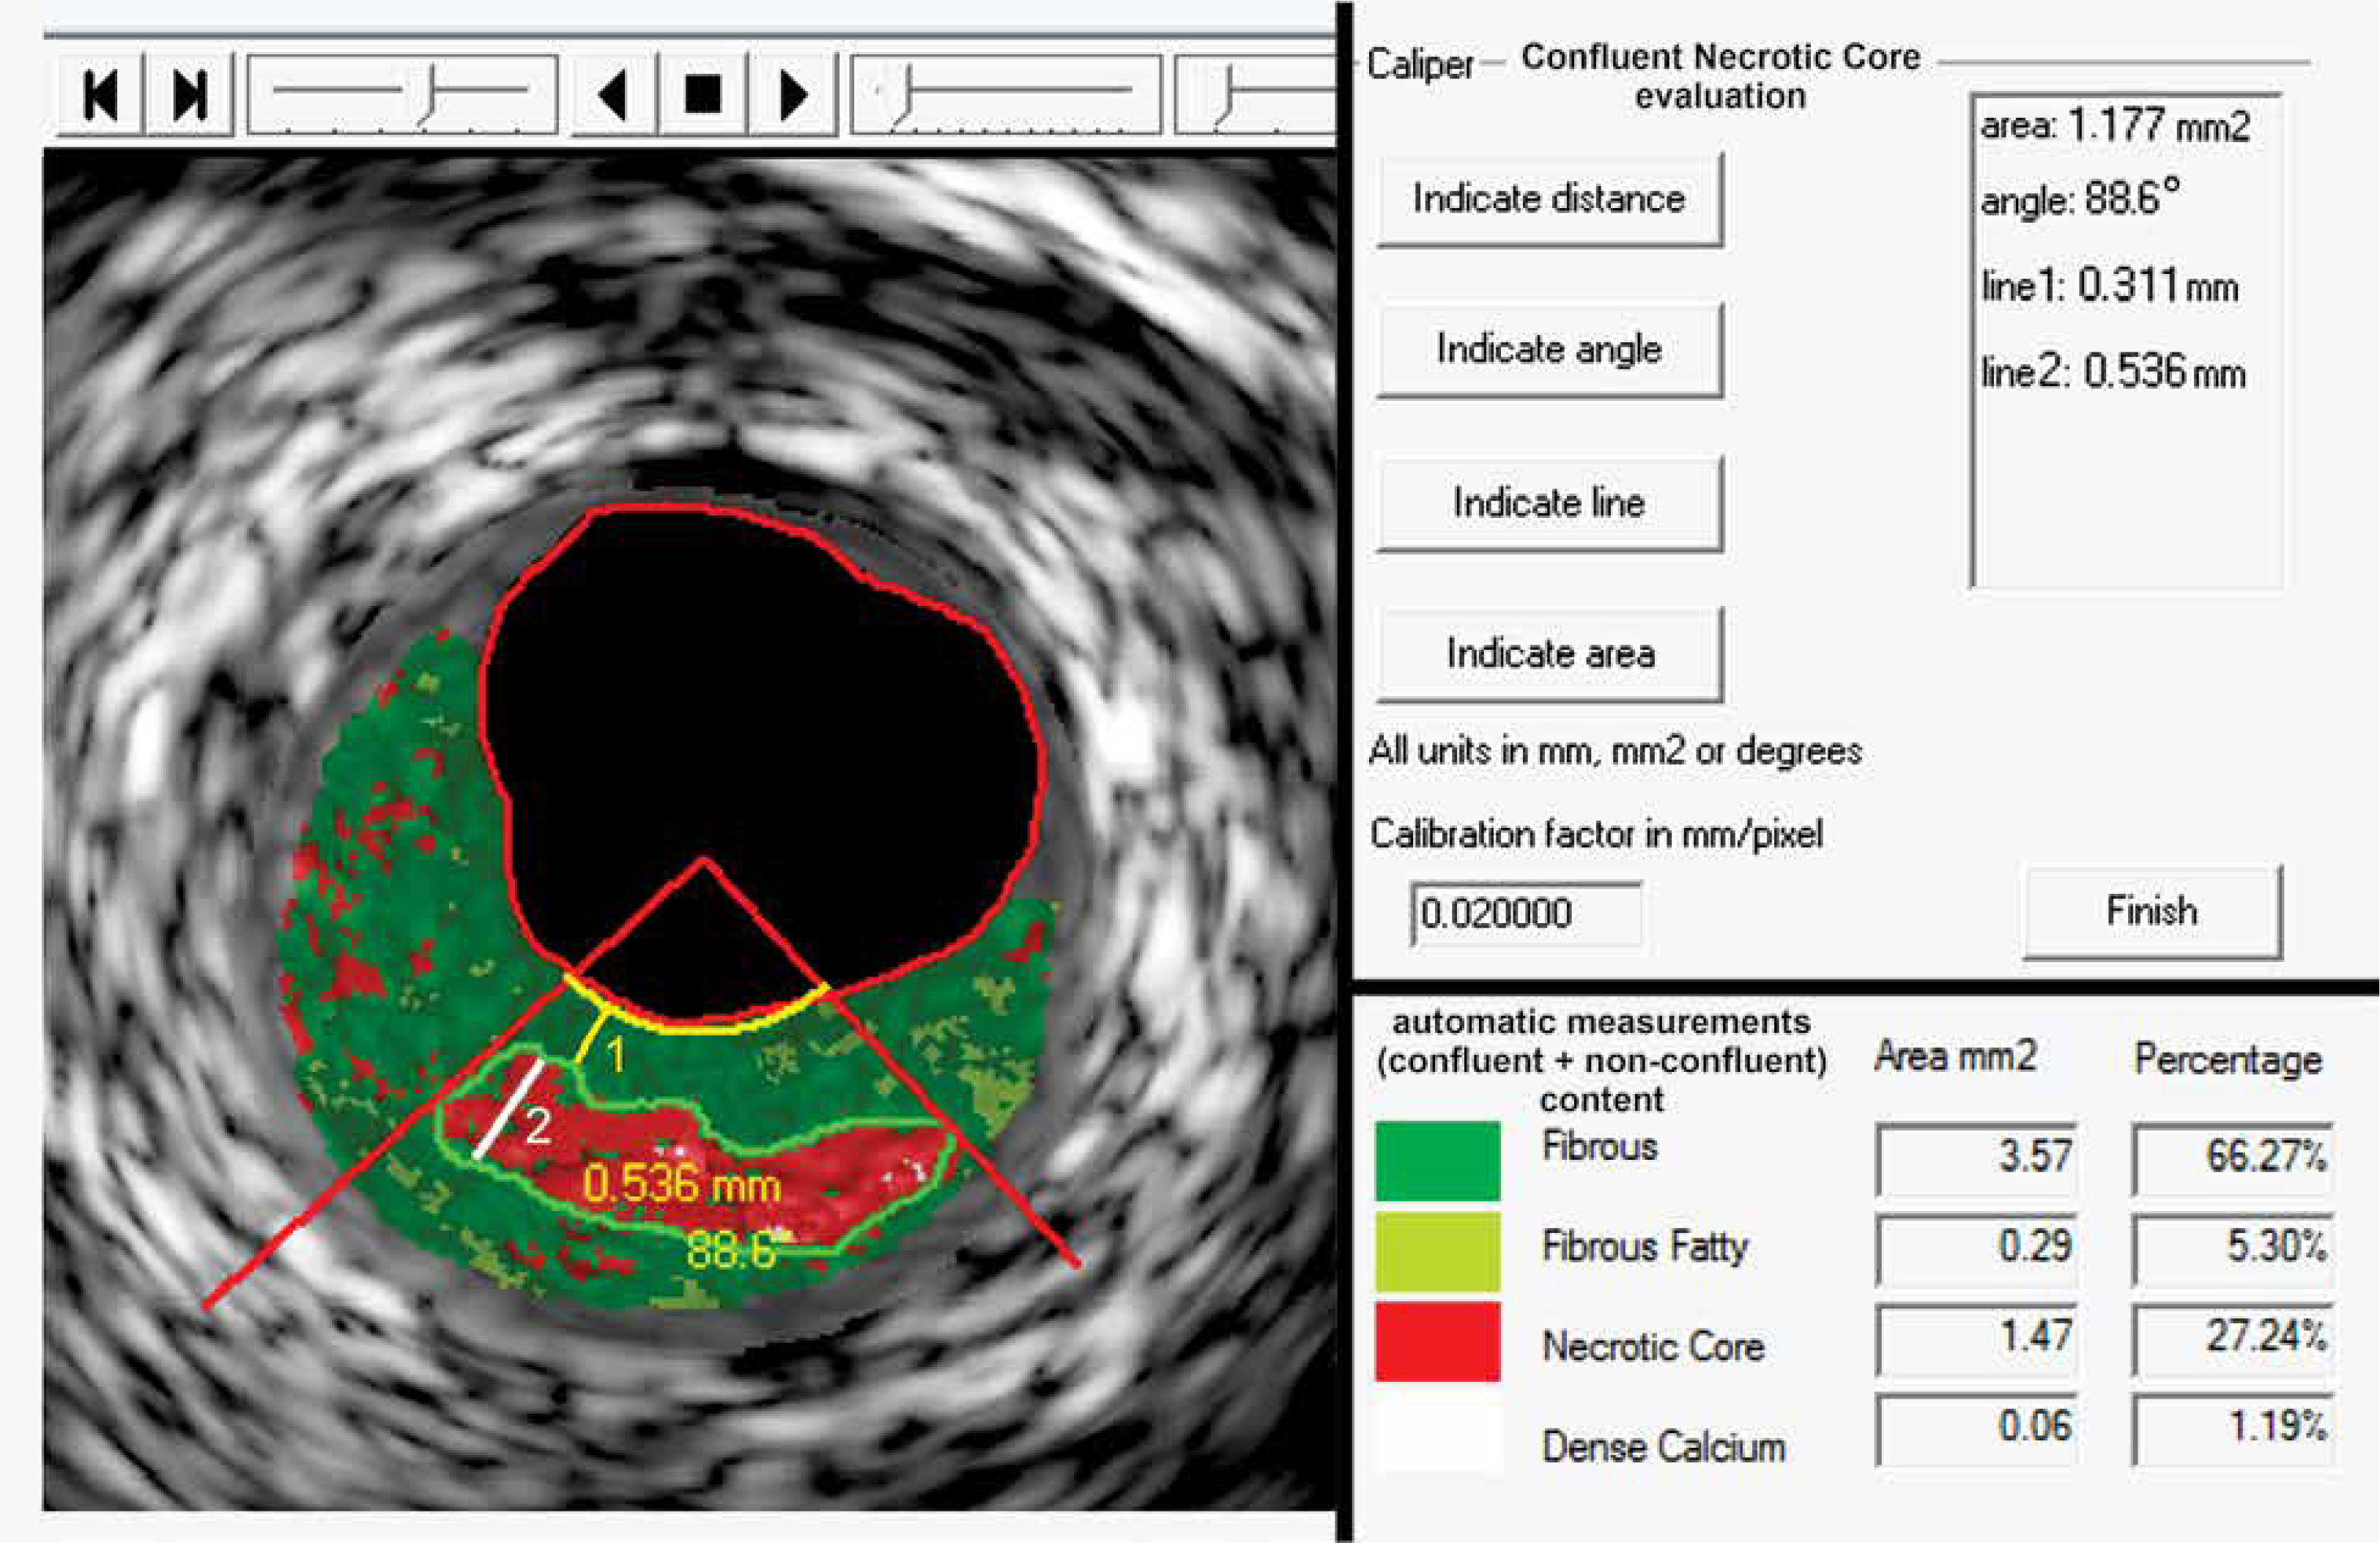

Figure 3

Typical example of quantification of key morphologic parameters of the atherosclerotic plaque using a novel image analysis algorithm (quantitative Virtual Histology, qVH). Commercially available software (QIvus 2.0, Medis Medical Imaging Systems, the Netherlands) was customized for qVH caliper and line tracking and was recently validated [21]. Confluent necrotic core is tracked on the left; numeric results of the measurements are shown in the top panel on the right. Necrotic core area – 1.177 mm2, necrotic core angle – 88.6°, peak necrotic core thickness – 0.536 mm. This contracts with the typical “automatic” software measurements (bottom panel on the right) that consider all pixels in a given color. Note that true necrotic core area is 1.18 mm2 rather than 1.47 mm2. The fibrous cap minimal thickness is 0.31 mm, consistent with a thick-cap fibroatheroma. Also note that the “automatic” software quantification provides a total (per cross-sectional area) content of each of the four principal VH-IVUS–detectable plaque components (fibrous, fibro-fatty, necrotic core, dense calcium), expressed in absolute units, mm2, or as proportion of the plaque area (%) but not of the parameters that are critical for plaque behavior in the context of rupture risk (cf., Figure 1). It may be important to realize that that the “automatic” quantification suffers from several types of artefacts, including the “calcium-associated” (pseudo) necrotic core [21, 29, 30]